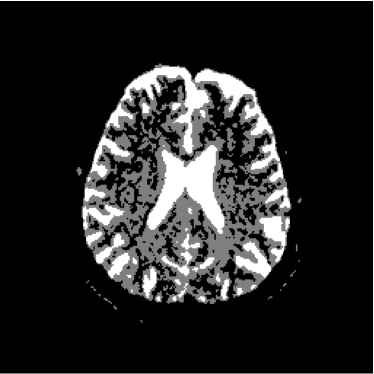

Therefore, the pixels of the ADC map are proportional to the diffusion coefficients in the corresponding voxels. However, as the images are acquired at different moments, there must be considered the occurrence of noise in all the experiments. Furthermore, the presence of noise is amplified by the use of the logarithm. In figures 7 and 8 it is possible to see several artifacts generated by the presence of noise. In regions where signal-to-noise ratio is poor (e.g. s/n1𝑠𝑛1s/n\approx 1), the ADC map produces artifacts as a consequence of the calculation of logarithms (notice equations 4 and 6).

Such factors leave us to the following conclusion: the pixels of the ADC map not necessarily correspond to the diffusion coefficients: several pixels indicate high diffusion rates in voxels where the sample are not present or in very solid areas like bone in the cranial box, as can be seen in figures 7 and 8. This is the reason why such map indicates apparent diffusion coefficients, and not real diffusion coefficients.

Refer to caption

Figure 7: ADC map of 13th slice calculated from the three diffusion images presented in figures 1, 2 and 3

Figure 8: ADC volume calculated from the volumes of figures 4, 5 and 6